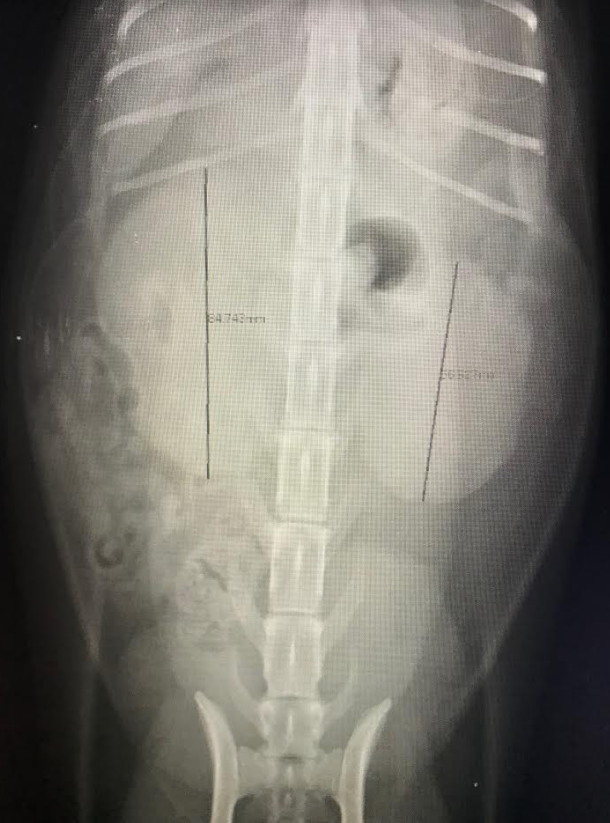

影像結果

X光顯示雙側腎臟腫大